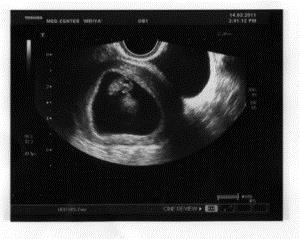

Знімки УЗД на 8 тижні вагітності